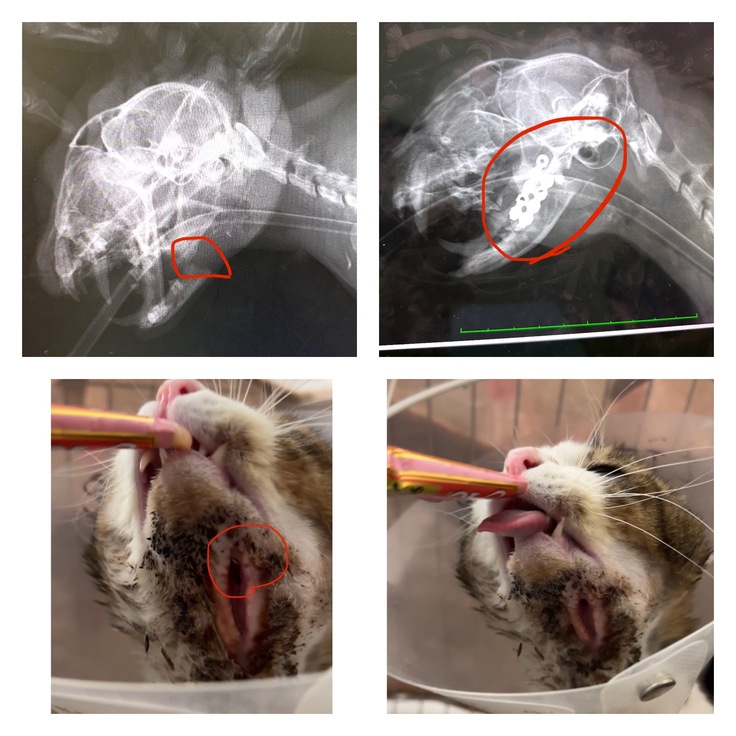

【歯の中に腫瘍などがないかチャックしてもらいました。きっちゃんは顎の骨折経験があり顎がズレて尖っていた歯が歯茎にあたるので削っています】

ある日、きっちゃんが、顎の骨が折れた状態で現れました。

診察の結果は、「顎の骨が折れている、大手術が必要です」と言われて。

それでも、迷いはありませんでした。ただ「助けたい、その一心でした。【骨が折れていたときはチュールも食べにくそうでした】

無事に手術は終わり、先生から言われたのは「治るまでの3ヶ月ほどは、家でケアしてあげてくださいね」という言葉。【ボルトを入れて顎の下は皮膚が薄く縫うことが難しく自然に皮膚が繋がるのを待つだけだったので痛々しいです。】

今思えば、あの時のきっちゃんとの出会いが、私が本格的に保護活動を始める“きっかけ”であり覚悟を教えてくれました。【顎がズレて舌が出るのですが、それがとってもかわいいです】